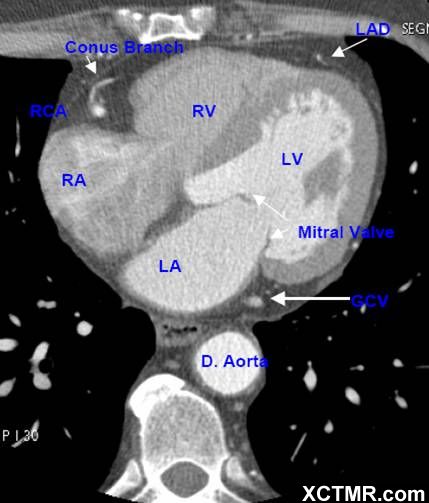

LA - Left Atrium 左心房

RA - Right Atrium 右心房

LV - Left Ventricle 左心室

RV - Right Ventricle 右心室

Mitral Valve 二尖瓣

D. Aorta-Descending Aorta 降主动脉

LAD - Left Anterior Descending Artery 左前降支

RCA - Right Coronary Artery 右冠状动脉

Conus Branch 右动脉圆锥支

GCV –Great Cardiac Vein 心大静脉